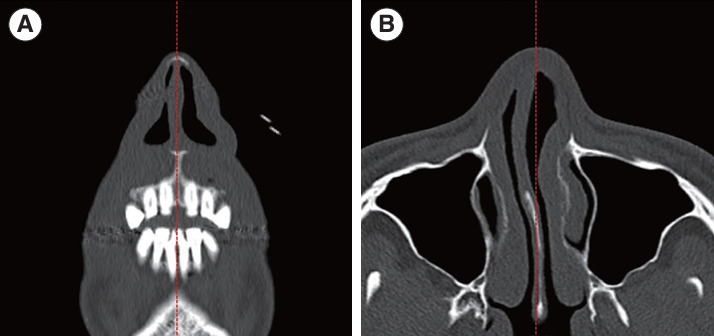

Methods: We analyzed 186 INVs in 93 patients who underwent nasal valve surgery. The data comprised facial computed tomography (CT) images, acoustic rhinometry, the modified Cottle test, and symptom scores. Patients were categorized based on their symptoms and the.

Results: of the modified Cottle test. We measured the INV angle, area, volume, lateral wall thickness, septal angle, and nasal bone area using CT.

Results: The compromised INV group, characterized by nasal obstruction with a positive modified Cottle test, exhibited smaller INV areas in both coronal and axial views, reduced INV volume in the axial view, and a thinner lateral wall in the coronal view (all P<0.05). Acoustic rhinometry indicated a smaller minimal cross-sectional area and volume in the compromised INV group (both P<0.001). Regression analysis demonstrated significant associations between a compromised INV and reduced INV area on the axial view, as well as the minimal cross-sectional area measured by acoustic rhinometry.

Conclusion: Relying solely on the INV angle in CT scans has limitations in assessing compromised INV. Alternatively, the INV area on axial CT scans and the minimal cross-sectional area measured by acoustic rhinometry may serve as objective parameters for evaluating INV compromise.